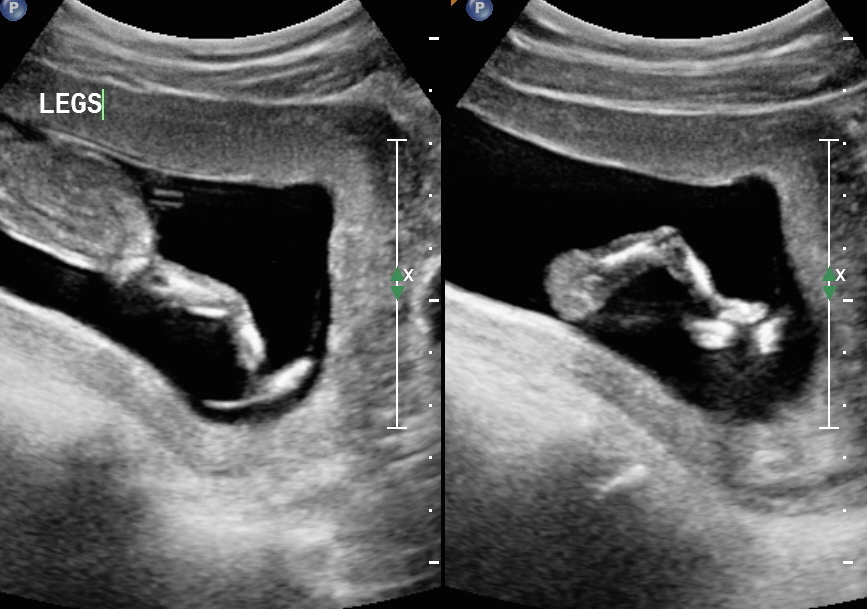

13 weeks 3 days. My first ultrasound. Tech wouldn't take a guess. Id love to know if any of you think girl or boy!!Attachment 25012Attachment 25013Attachment 25014

I'm sorry, I don't see a nub, but will give a boy skull guess just for fun! (not reliable!)

Nope they did a good job keeping that nub hidden from view on the angles they chose.

Not seeing any clue, sorry...